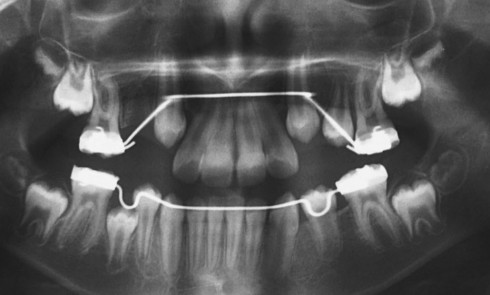

Situation clinique initiale Lina, 8 ans et 5 mois, nous est adressée en consultation d’orthodontie dans le service de médecine...